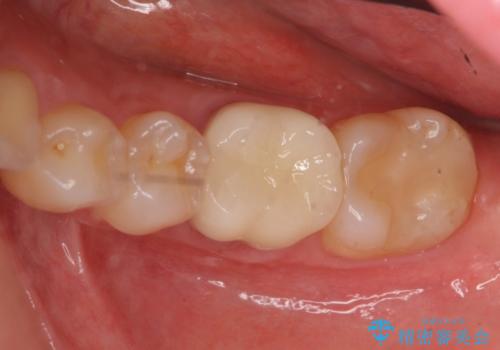

セラミックインレー 下の一番奥歯 歯ぐきの厚みを減らしてぴったりに入れます(ディスタルウェッジ+骨外科)

ただし、元のインレーが遠心マージンが縁下だったため、矯正治療後に歯ぐきの厚みを減らして、しっかり歯ぐきの上にマージンラインが来るように整える手術(ディスタルウェッジ)を行いました。

手術後、きちんとマージンラインが歯肉の上に来た状態で、セラミックインレー修復を行いました。